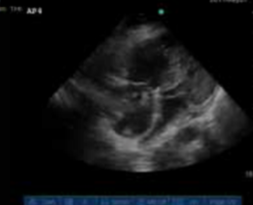

Increased LV ejection fraction, increased volume in the right ventricle and a “D-shaped” septum

Acute RV overload due to PE (RV strain). Note that it is easy to mis-identify the RV in these cases because it is so much larger.